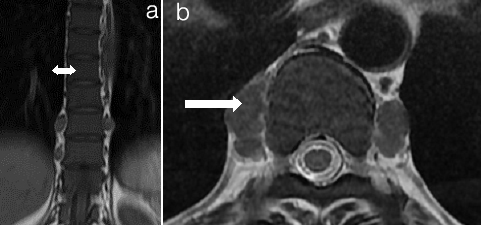

Avascular necrosis of femur head mri (ficat and arlet) (a) Right Grade II Left Grade I (b) Right Grade II Left Grade IV C .Left Grade III (a) Cor T2WI hip joint shows hyperintense signal suggestive of oedema FICAT Grade I (thin white arrows in a). There are multiple infartcs in head, neck and shaft of right femur showing hyperintense signal with hypointense rim (arrows in a) FICAT Grade II. Reduced signal of marrow suggesting red marrow in both femur. Bilateral hip joint effusion. (b) T1WI shows Crescent sign in head of right femur consisting inner hyperintense rim with outer hypointense sclerotic rim FICAT Grade II (curved arrow in b). There is collapse of head on left side with crescent sign and reduced joint space FICAT Grade IV (white arrow in b). (c). Cor T2WI shows flattening and reduced signal with crescent sign in head of femur on left side (arrow in c) suggesting Grade III AVN with joint effusion. Note infarcts in bilateral iliac bones

Bony infarcts at multiple sites a) Pelvis STIR b) Left Humeral neck T2WI c) Left Humerus epiphyseal infarct T2WI d) T2 Weighted Image a) Cor STIR of Pelvis shows multiple areas of hyperintense signal in iliac bones, sacrum and left femur neck suggesting infarcts (arrows in a). b) and c) Cor T2WI Head and neck of left humerus shows altered signal intensity areas with a hypointense rim suggesting infarcts (arrow in b, curved arrow in c) . d) T2WI of the vertebral column shows multiple vertebral bone marrow infarcts with infective pre and paravertebral collection